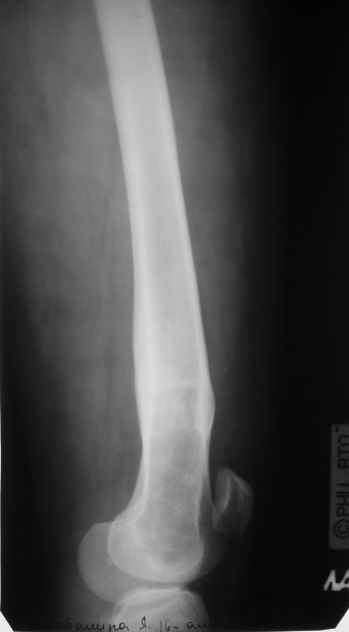

Пациентка 23 лет, доставлена в клинику с Диагнозом: Закрытый сегментарный оскольчатый перелом левой бедренной кости в верхней и средней трети. Травма в результате ДТП 10.03.2006г. Из анамнеза у пациентки диспластический левосторонний коксартроз, S-образный сколиоз 2ст. В 1999г в Кургане выполнялась остеотомия бедра в нижней трети и коррекция укорочения конечности на 3 см (рентгенограммы бедра и таза до травмы в приложении). До получения травмы пациентка ходила без боли с полной нагрузкой на левую ногу. Учитывая дисплазию левого ТБС, пациентке, вероятно, предстоит операция тотального эндопротезирования лев ТБС, что требует анатомичного восстановления проксимального отдела бедра.

Рассматриваются следующие вариант остеосинтеза: 1) Экстракортикальный остеосинтез проксимального и дистального перелома пластиной с угловой стабильностью типа LISS( г Рыбинск);

2) Ретроградный интрамедуллярный блокированный остеосинтез дистального перелома и накостный синтез проксимального пластиной с угловой стабильностью;

3) Остеосинтез бедра в аппарате внешней фиксации с фиксацией таза и возможной открытой адаптацией фрагментов.